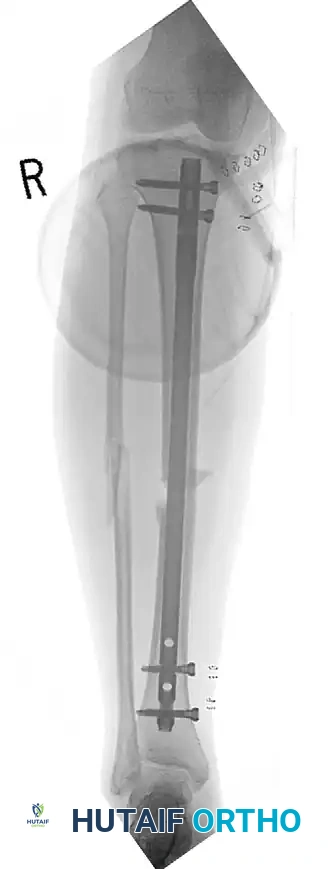

المسامير النخاعية لعظام الفخذ والساق

تدعم الأدلة الطبية الحديثة استخدام المسامير النخاعية المقفلة كعلاج مفضل لمعظم كسور الفخذ والساق. يتم إدخال مسمار معدني قوي داخل التجويف النخاعي للعظم لتثبيته من الداخل. أثبتت الدراسات أن التثبيت الفوري بالمسامير النخاعية، حتى في حالات الإصابة بالطلق الناري، يقلل من فترة البقاء في المستشفى ولا يزيد من معدلات العدوى إذا تم التنظيف الجراحي بشكل صحيح.

في حالات الكسور شديدة التلوث والدمار النسيجي، يطبق الأطباء مبدأ جراحة التحكم في الأضرار. يتم تثبيت الكسر مؤقتاً باستخدام مثبت خارجي حتى تتعافى الأنسجة الرخوة المحيطة، وبعد أسبوعين تقريباً، يتم تحويل التثبيت الخارجي إلى تثبيت داخلي دائم بالمسمار النخاعي.